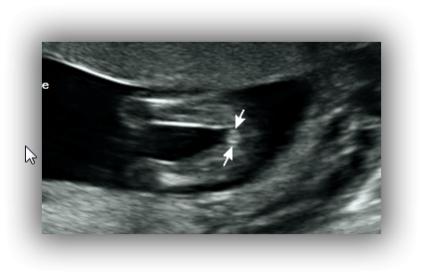

Hi, potty shot at 13w5d - any idea on gender and accuracy? Can it still change?

Potty shots aren't all that reliable at that point but I don't see anything that screams boy. Looks girly to me. Your signature says you're having twin girls? Did you find out from a blood test?

Thank ksmom. I went for a private scan and I was just querying this one as it looks so different to the other twin's potty shot, but also, some people with twins said that because there are 2, the growth of the babies might be a little slower than with a singleton and some had wrong genders given at more or less same gestation.

I know its just wishful thinking on my part, but I was just wondering if perhaps I'm missing something. Also doesn't look very boyish to me.